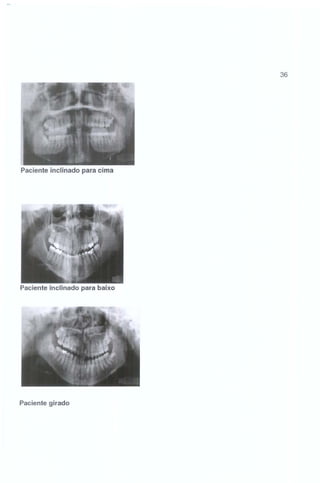

36

Paciente inclinado para cima

Paciente inclinado para baixo

Paciente girado